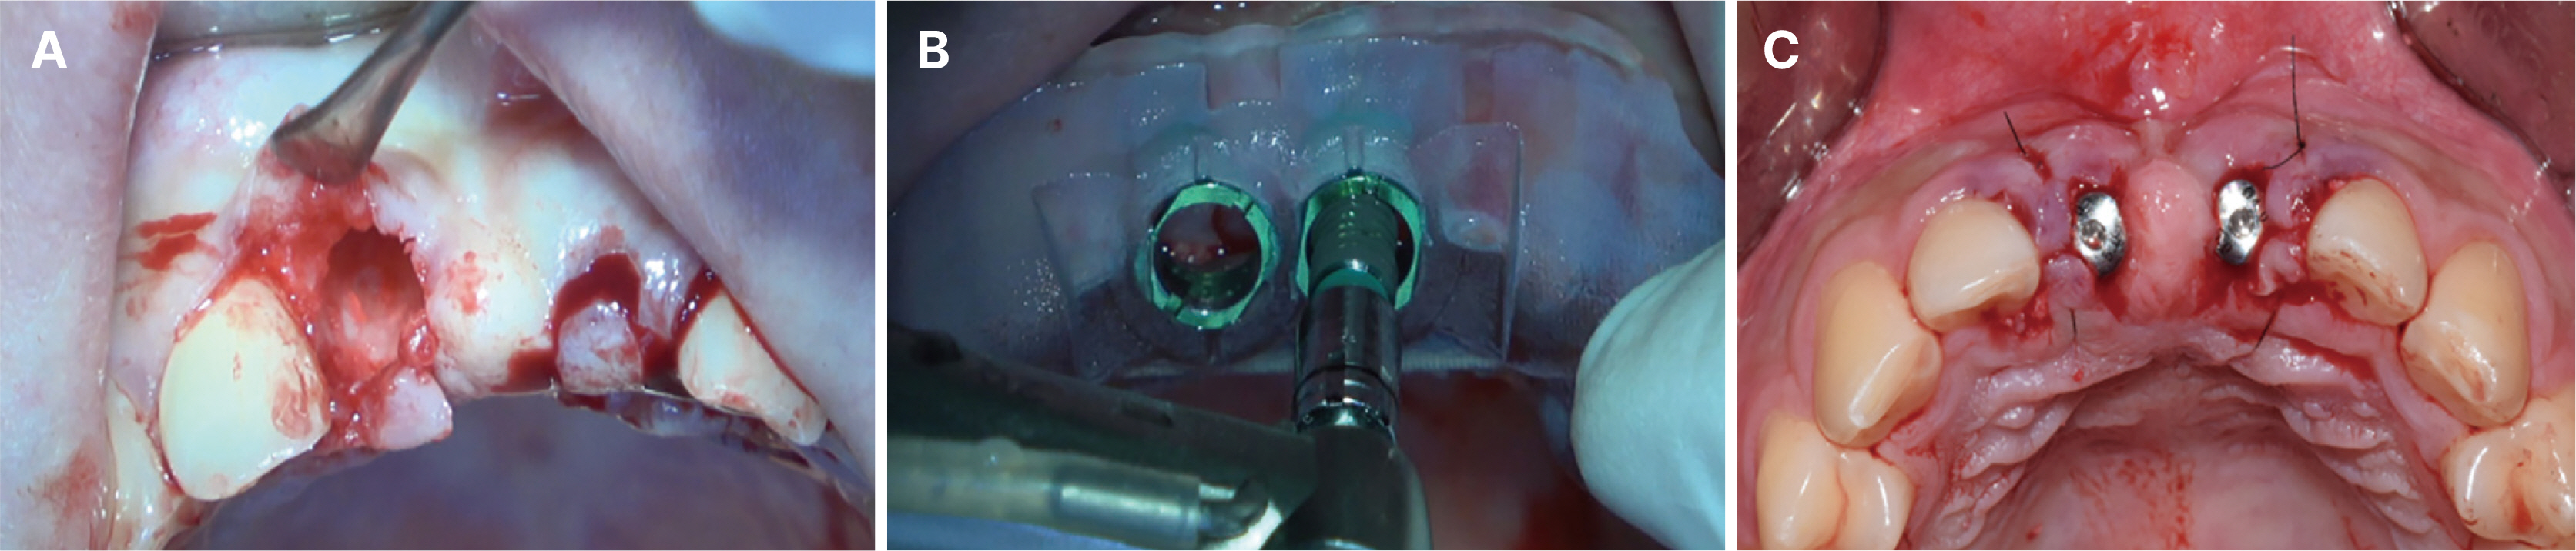

- Immediate implant placement and immediate loading in the anterior maxilla is an effective approach to rapidly address aesthetic demands. To achieve successful outcomes, bone quality, soft tissue condition, and accurate implant positioning are essential factors. For optimal results, procedures such as bone augmentation, precise implant placement, and, when necessary, soft tissue grafting should be considered. Furthermore, provisional restoration play a crucial role in achieving the desired appearance of prosthetic restorations and improving the aesthetics of the soft tissue. By performing soft tissue molding through provisional restoration, an ideal emergence profile can be established, which can be subsequently transferred to the final prosthesis, leading to a functional and aesthetically pleasing restoration. This approach aims to optimize the aesthetic outcomes in the anterior region while preserving the natural contours of the peri-implant soft tissue. In this case, a patient requiring extraction of maxillary anterior tooth underwent immediate implantation and alveolar bone grafting using a guide fabricated in advance from CT data. The patient received a provisional restoration on the same day. Subsequent steps included transitioning from the provisional prosthesis to the definitive prosthesis, ultimately achieving an aesthetically pleasing and functional implant restoration. We report this case to highlight the successful approach to maxillary anterior implant rehabilitation.